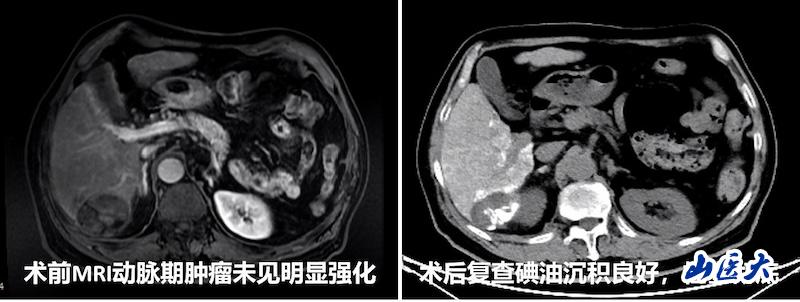

手術過程中,在CBCT的實時引導下,團隊精準鎖定患者腫瘤的三支供血動脈,并利用微導管逐一超選至目標血管,順利完成化療栓塞。栓塞后造影顯示腫瘤血管完全消失,病灶碘油沉積良好。術后一周復查CT,碘油沉積范圍與PET/CT提示的活性病灶范圍完全一致,治療效果明顯。